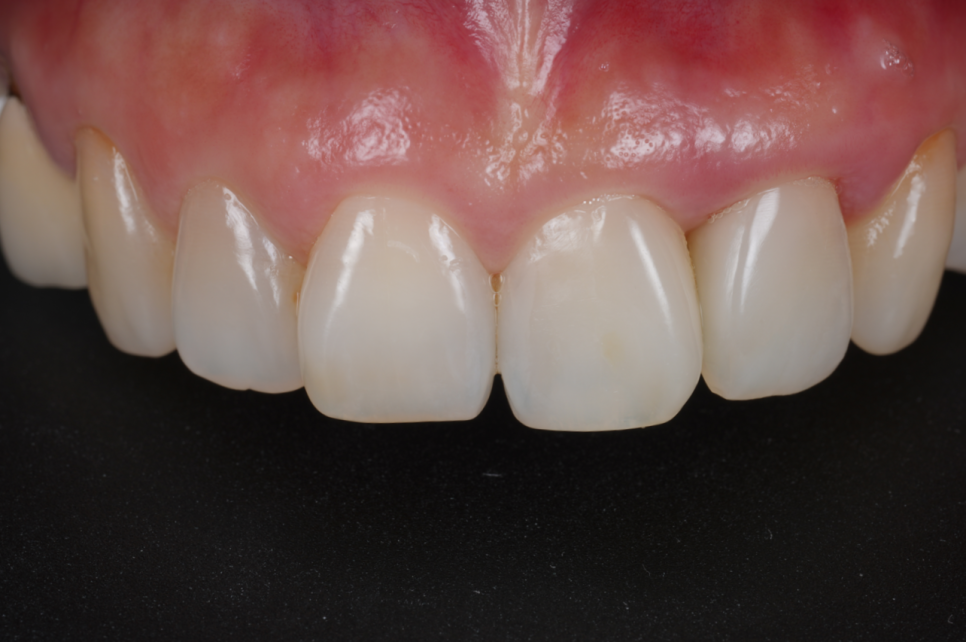

1주 뒤, 경과체크를 했습니다.

260107

잇몸이 아주 잘 아물었습니다.

잇몸 라인이 건강하게 정리되니 웃을 때 치아도 훨씬 황금비율에 가까워졌는데요.

또한 왼쪽 아래 어금니도 지르코니아로 씌워 심미와 기능 모두 회복하셨습니다.

251230/260107